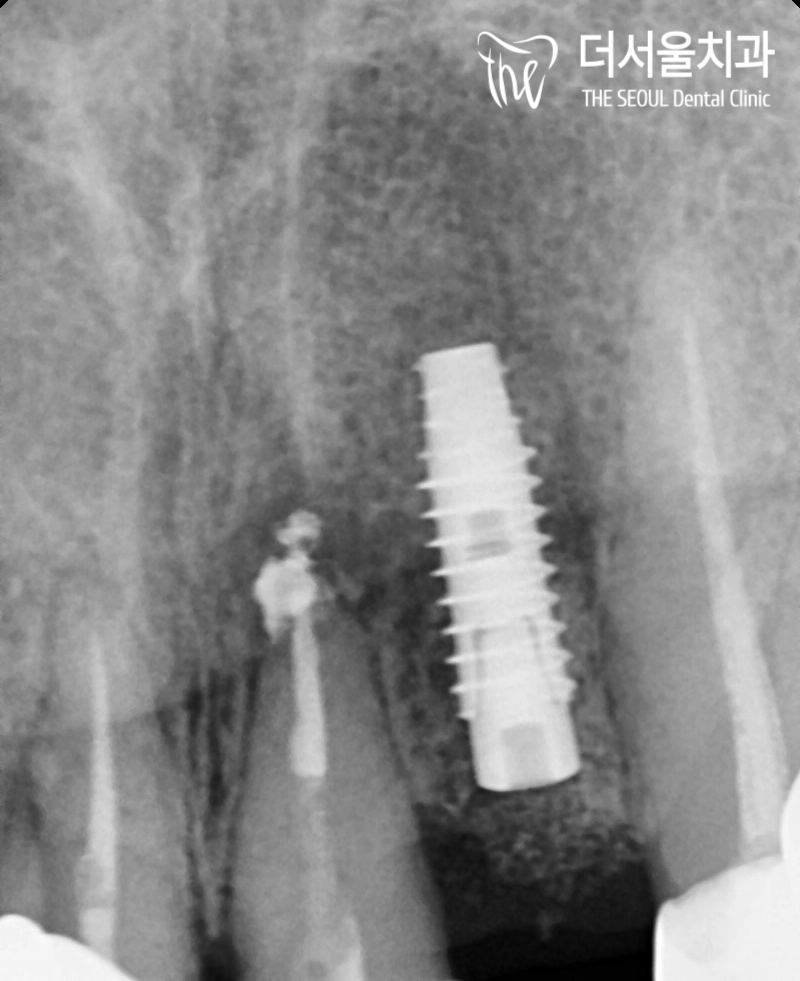

# 22를 발치 후 픽스처를 심었고,

뼈와 고정될 수 있도록

골유착 기간을 가졌습니다.

오랜 기간이 걸리더라도

뼈와 골유착이 잘 이뤄지지 않으면,

쉽게 떨어져 재수술을 받아야 될 수 있습니다.